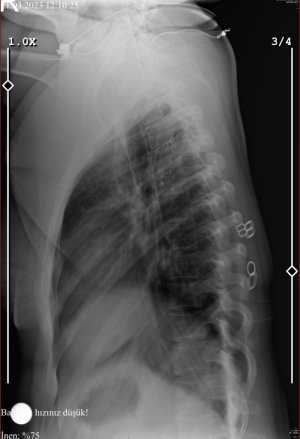

Merhabalar, 25 yaşındayım 1 senelik evliyim ve çocuk düşünüyoruz. Spor salonunda çalışıyorum sürekli klima altında ve farında olmadan bende çoğunlukla postürümü bozabiliyorum. Geçmeyen kulunç ve ağrılarım için doktora gittiğimde röntgen çektirdim. Hafif skolyoz, ileri derecede boyun ve ileri derecede bel düzleşmem olduğu söylenildi. Pazartesi günü fizyoterapistin isteğiyle mr çektireceğim. Size sorum şu eğerki düzleşmeyse bu sorunlar fizik tedavi ve akışkanlıklarla normale dönebilir fakat bel ve boyun fıtığıysa da ameliyatsız tamamen iyileşir mi? Tabiki bu süreci doğru bir şekilde atlatmadan ağrılarım geçmeden ya da düzelmeden hamilelik durumunu ileriye almam gerekiyor. Korkularımdan bir tanesi de olduki iyileştim fakat hamilelik sonrası tekrardan nüks etti neler yapabilirim bu konu için.Lütfen beni aydınlatıp yardımcı olabilir misiniz….

B97C896E-312D-4DDC-87F2-53849FB53C10.jpeg163,8 KB · Görüntüleme: 61

057DE076-C50D-424A-A67D-EDDF3D5F93BA.jpeg229,4 KB · Görüntüleme: 55

0F0602B4-ACCD-46AD-8196-2FAF80642ED5.jpeg73,9 KB · Görüntüleme: 47

96EEF17C-7771-4848-887F-A2522981576E.jpeg74,6 KB · Görüntüleme: 50

FEBCE1CC-76B0-40B2-99C7-B96B90EC6CA8.jpeg78,1 KB · Görüntüleme: 52

AC7A1152-42B7-49CE-86F1-CA0E86ED914F.png125,5 KB · Görüntüleme: 53